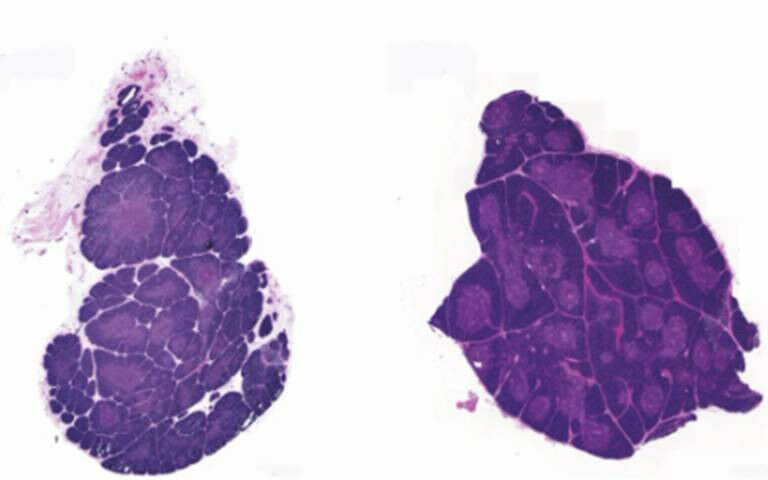

The new images reveal the inner structure of the thymus and shed light on the size and evolution of areas called Hassall’s bodies, which form around 15 weeks into pregnancy. Until recently they were considered onion-like structures defined as the ’graveyard of thymocytes’.

The researchers showed that structures called Hassall’s bodies appear early during organ development and occupy about a quarter of the medulla in the thymus in children when the thymus is most active, suggesting that they play a role in immune regulation.

The team confirmed that both the synchrotron and the edge-illumination system were able to distinguish between the cortex and medulla, as well as show Hassall’s bodies, in images of a 19-day-old thymus.